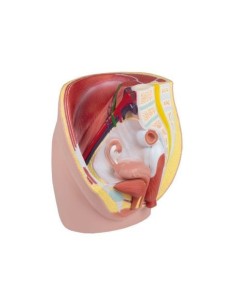

3B Modèle scientifique et gynécologique pour l'entretien avec les patientes P53

3B Scientific. Kit d'enseignement, système de reproduction femelle W40214